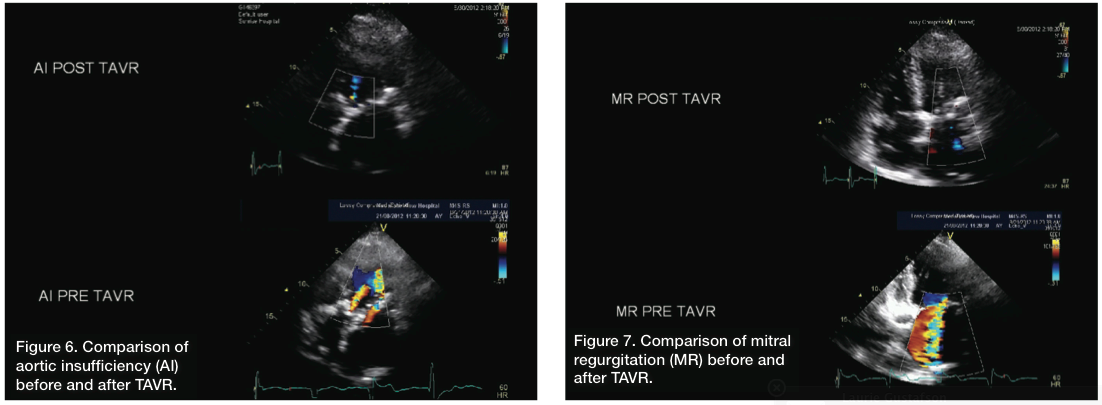

The patient was recovered and extubated in the hybrid operating suite. Her hemodynamics were stable overnight. On post-operative day 1, she was ambulating, with improvement in dyspnea. An echo obtained twenty-four hours post procedurally was remarkable, with complete abolishment of the previously seen aortic regurgitation, and more surprisingly, near complete abolishment of the mitral regurgitation (Figures 6-7). LV size also appeared smaller and function had improved, with an ejection fraction of about 45%. The patient was uneventfully discharged from the hospital by post-operative day 4.